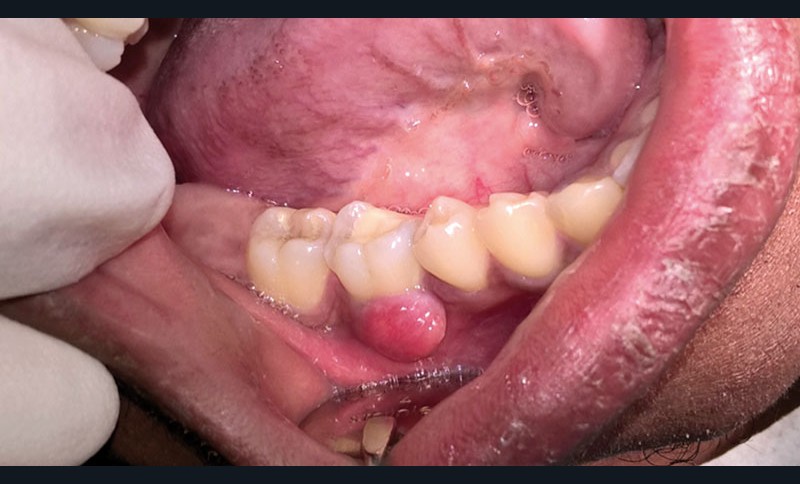

Lorsqu’un patient se présente en consultation avec une lésion au contact d’une dent (fig. 2), le praticien doit suivre une démarche diagnostique afin de recueillir le maximum d’informations sur la situation clinique :

anamnèse et historique bucco-dentaire du patient ;

évaluation des symptômes : douleur, gêne fonctionnelle, doléance esthétique ;

état général;

sondage parodontal à l’aide d’une sonde graduée (fig. 3) de tout le quadrant d’arcade;